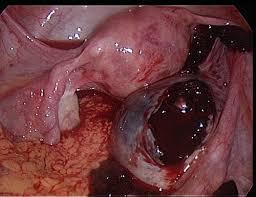

Апоплексия яичника - это произошедшее внезапно нарушение целостности ткани женского яичника с последующим кровоизлиянием в брюшную область. Апоплексия сопровождается острыми болями в области нижних отделов живота, обусловленных раздражением брюшины.

Механизм апоплексии яичника основан на разрыве фолликула во время овуляции для прохождения яйцеклетки наружу. На месте разрыва формируется желтое тело, производящее необходимые гормоны. Обычно разрывы бывают небольшими и быстро восстанавливаются. Но в патологических случаях может произойти разрыв достаточно глубокий, с повреждением крупного кровеносного сосуда и тогда происходит кровоизлияние в брюшную полость. Причем кровеносные сосуды в месте разрыва теряют сократительную функцию, и кровотечение самостоятельно может не остановиться, приводя к развитию гематомы желтого тела.

Наиболее эффективным методом диагностики апоплексии являются ультразвуковое обследование, с подтверждением наличия крови в области живота и остаточной полости яичника, а также лапароскопия, при которой кроме установления диагноза возможно проведение остановки кровотечения (гемостаза), т.е. переход диагностической лапароскопии в лечебную.

Эндовидеоскопическая хирургия рекомендована и при легкой степени разрыва яичника. Эта операция при апоплексии яичника носит щадящий характер, при ней удаляют кистовую капсулу, ушивают яичник или перевязывают поврежденные сосуды, кроме того убираются остатки крови и сгустков путем промывания брюшной полости. В исключительных случаях проводят удаление яичника.